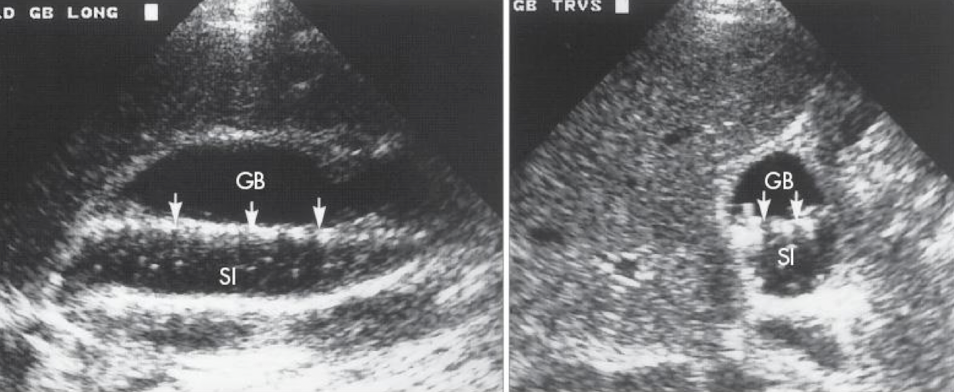

chronic cholecystitis

recurrent attacks of acute cholecystitis with fibrosis of GB wall

s/s: neg. Murphy’s; RUQ pain but no tenderness

SONO:

neg. Murphy’s sign

contraction of GB

stones

WES sign

WES (wall echo shadow)

indicative of a stone-filled GB (GB is a packed)

3 arched-shaped line

shadow posterior to 3rd line

??

cholelithiasis